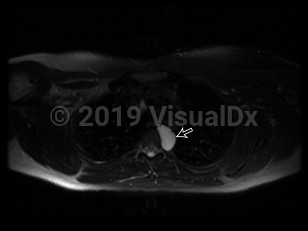

A bronchogenic cyst is a congenital respiratory tract malformation arising as an embryonic out-pouching of the foregut or trachea. Bronchogenic cysts can be found anywhere along the tracheobronchial tree and are often asymptomatic unless they become infected. Cysts typically appear as sharply marginated, water-density lesions on chest x-ray and may contain air-fluid levels when infected.